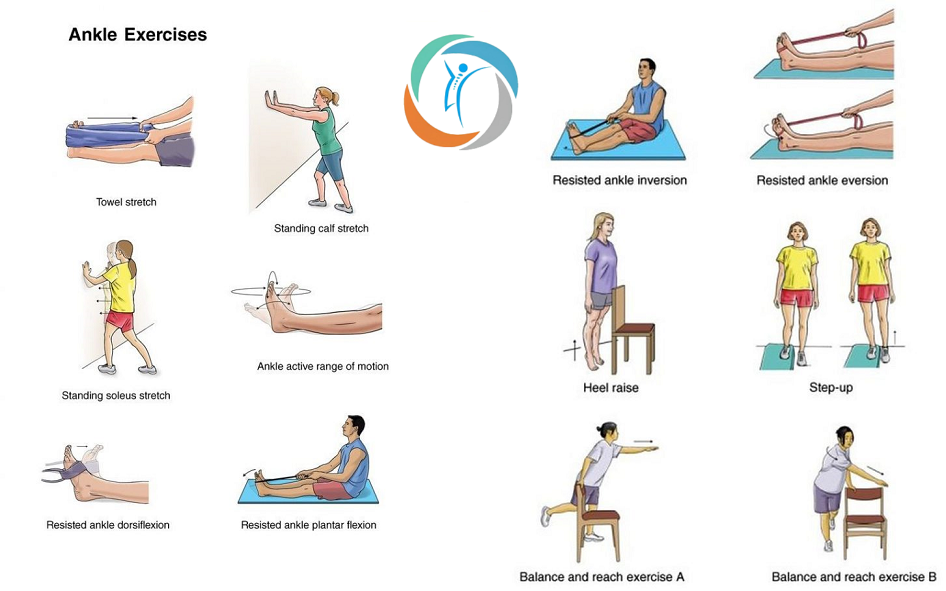

پیچخوردگی مچ پا معمولاً در اثر چرخش ناگهانی یا نامناسب پا رخ میدهد. در این شرایط، استراحت کافی، استفاده از کمپرس سرد برای کاهش التهاب، بستن باند کشی و بالا نگه داشتن پا از اصول اولیه درمان محسوب میشود. مصرف داروهای ضدالتهاب غیراستروئیدی مانند ایبوپروفن نیز میتواند در کنترل درد و التهاب مؤثر باشد. پس از مرحله حاد، فیزیوتراپی برای بازگرداندن دامنه حرکتی و قدرت عضلات توصیه میشود.

🔥 التهاب تاندونها (تاندونیت)

در موارد التهاب تاندونهای اطراف مچ پا، کاهش فشار بر ناحیه آسیبدیده، استراحت، استفاده از یخ و مصرف داروهای ضدالتهاب از جمله اقدامات اولیه درمانی است. بسته به شدت آسیب، استفاده از آتل و انجام تمرینات فیزیوتراپی تحت نظر متخصص میتواند روند بهبودی را تسریع کند.

🦴 آرتریت و ساییدگی مفصل

در شرایطی مانند آرتروز یا نقرس، مفصل مچ پا دچار التهاب، سفتی و درد میشود. درمان این بیماریها شامل داروهای ضدالتهاب، کنترل دقیق بیماری زمینهای و استفاده از کفش یا کفی طبی برای کاهش فشار بر مفصل است. همچنین انجام حرکات کششی و تمرینات سبک به منظور حفظ تحرک مفصل توصیه میشود.

پیشگیری از علت درد مچ پا

انتخاب کفش مناسب با پشتیبانی کافی برای جلوگیری از علت درد مچ پا

- تقویت عضلات پا با تمرینات منظم برای پیشگیری از علت درد مچ پا